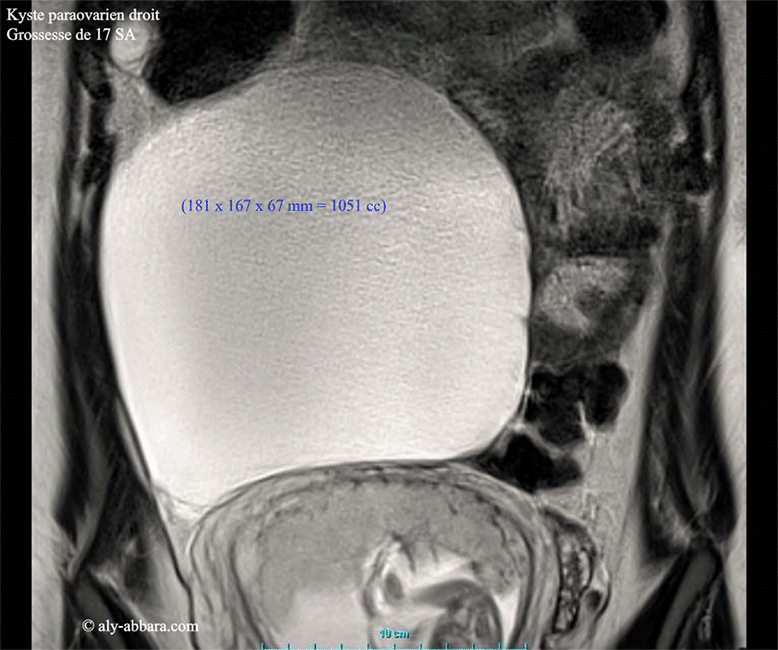

Kyste paraovarien droit chez une femme enceinte de 17 SA - IRM

Il s'agit d'un kyste uniloculaire de 181 x 167 x 67 mm de dimensions (soit environ 1051 cm3 de volume), à paroi fine, sans végétations endophytiques et sans épanchement péritonéal.

Cette tumeur kystique a été découverte fortuitement lors d'un examen échographique chez une patiente âgée de 19 ans, enceinte de 17 SA. Il s'agit formation kystique oblongue évoluant dans la cavité abdominale, hors de pelvis et prenant sa racine des annexes utérines droites.